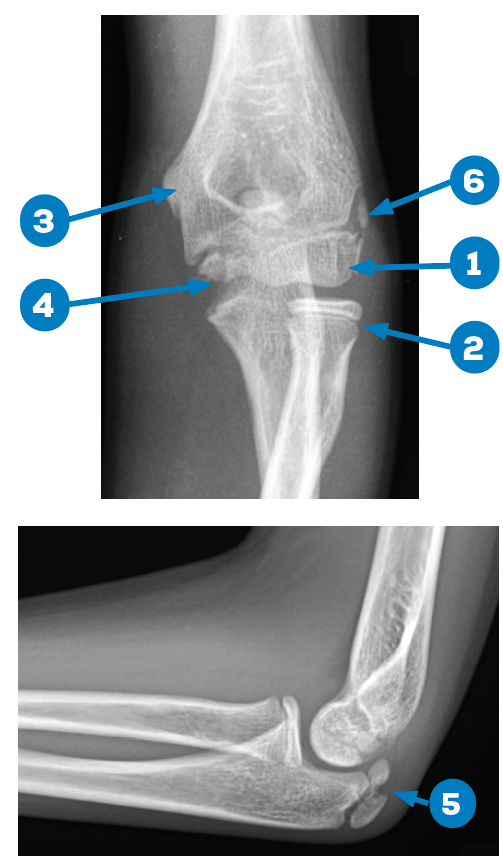

X Ray Elbow Normal

Normal elbow radiographs | Radiology Case | Radiopaedia.org Normal elbow x-ray - 7-year-old | Radiology Case | Radiopaedia.org Normal elbow series | Radiology Case | Radiopaedia.org File:X-ray of normal elbow by lateral projection.jpg - Wikimedia Commons | X Ray Elbow Normal